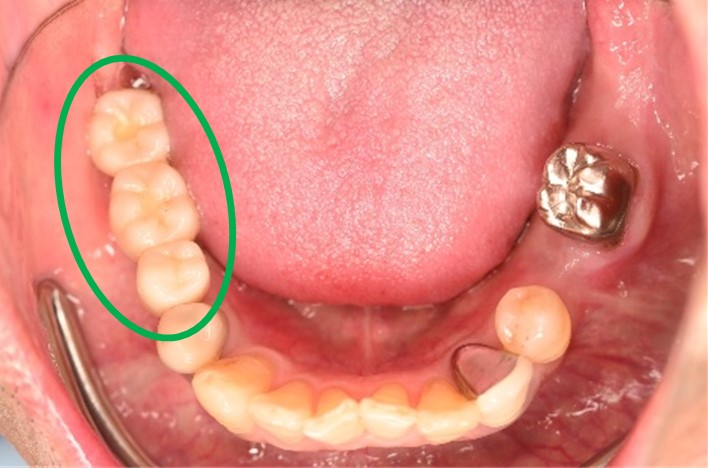

男性 Kさん 60代 (インプラント)

主訴

下の左右歯がないところに歯を入れたい。

治療内容

左右それぞれ3本歯がないところに2本ずつインプラントを埋入しました。

所感

上と下の歯の咬合接触がないすれ違い咬合です。上下義歯で対応するには最も難しいタイプの欠損状況です。治療開始前は、上下部分入れ歯が入っていましたが、入れ歯の安定が悪く、あちこちの歯茎に入れ歯が当たって痛く、満足に噛める状態ではありませんでした。上顎は、残ってる歯を活用するマグネット式総義歯を、下顎はインプラントを提案しました。上顎は、現在残っている歯の根管治療中です。上顎にマグネット式総義歯がはいれば、何でも食べられるようになります。

インプラント4本:¥363,000×4本=¥1,452,000(税込)

ポンティック2本:¥115,500×2本=¥231,000(税込)

合計:¥1,683,000(税込)

Before

▼初診時に使用していた部分入れ歯を装着したところ

▼インプラント埋入前

After

▼インプラント埋入後